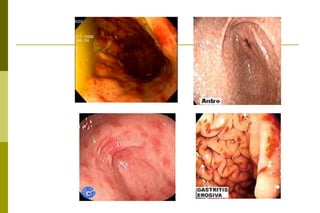

Gastropatia aguda:Reação aguda da mucosa gástrica frente a agentes variáveis.Dura +\- 5 dias e cessada a causa, a mucosa volta a normalidade. Etiologia:- Medicamentos (aspirina);                - bebidas alcoólicas               - estresse               - sais biliares               - álcalis e ácidos fortes               - intoxicação alimentar               - agentes biológicos (vírus, bactérias).

Gastropatia aguda:  Mecanismos patogênicos mais comuns:aumento da secreção ácida. redução da produção de íons HCO3-. lesão direta da parede da mucosa  permitindo a retrodifusão de íons H-.

Gastropatia aguda: Macroscopia:Enantema esparso, difuso, petequial

Erosões

Sinais de sangramento recenteMicroscopia:         - presença de erosões edema

fibrina

exsudato inflamatório: predomínio de neutrófilos

Gastrite crônica:Tem início insidioso, de evolução lenta e gradativa ao longo de anos ou décadas. São assintomáticos ou oligossintomáticos. O diagnóstico histológico da gastrite crônica se baseia na presença da reação inflamatória na mucosa caracterizada por exsudato de mono e polimorfonucleares, em proporção e intensidade variáveis

Classificação das gastrites crônicas:Gastrite antral(tipo B) tem etiologia bacteriana (H. pylori). Gastrite do corpo (tipo A) etiologia auto-imune (desenvolvimento de Ac contra células parietais). Atinge a mucosa oxíntica e pode evoluir rápido para atrofia. A mucosa do antro parece normal. Pangastrite (tipo AB) também de etiologia bacteriana."Diferentes cepas associadas as diferentes reações do hospedeiro levam a instalação de um dos tipos ". Têm maior tendência ao aparecimento de alterações do crescimento e diferenciação celular do epitélio glandular do que aqueles com gastrite somente antral.

Gastrite antral(tipo B) tem etiologia bacteriana (H. pylori).  Avaliar à macroscopia:- enantema :  esparso, difuso                      leve, moderado e intensoáreas sugestivas de metaplasia intestinal

Gastrite antral(tipo B)